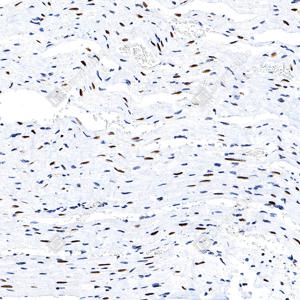

| IHC检测phospho-STAT1 (S727)蛋白(货号 GB150117). 样品: 小鼠心, 4%多聚甲醛 (货号G1101) 固定12-24小时. 抗原修复: Tris-EDTA抗原修复液(pH 9.0) (G1203), 100℃, 25分钟. —抗: 1: 8000稀释, 4℃ 孵育过夜. 二抗: S-vision免疫组化多聚二抗(山羊抗兔),即用型 (货号G1302), 室温孵育20分钟. |